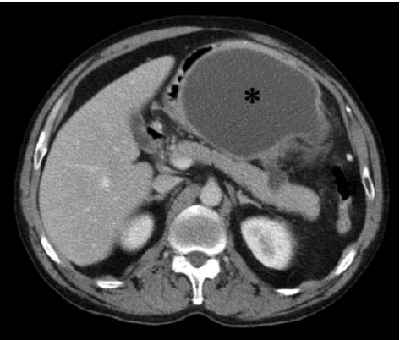

Figura 9: imagen TC pseudoquiste pancreático.

Imagen quística con pared bien definida, con contenido líquido, en el sector anterior del epigastrio (asterisco) y pequeña imagen líquida conectando con la cara anterior del páncreas en el cuerpo.